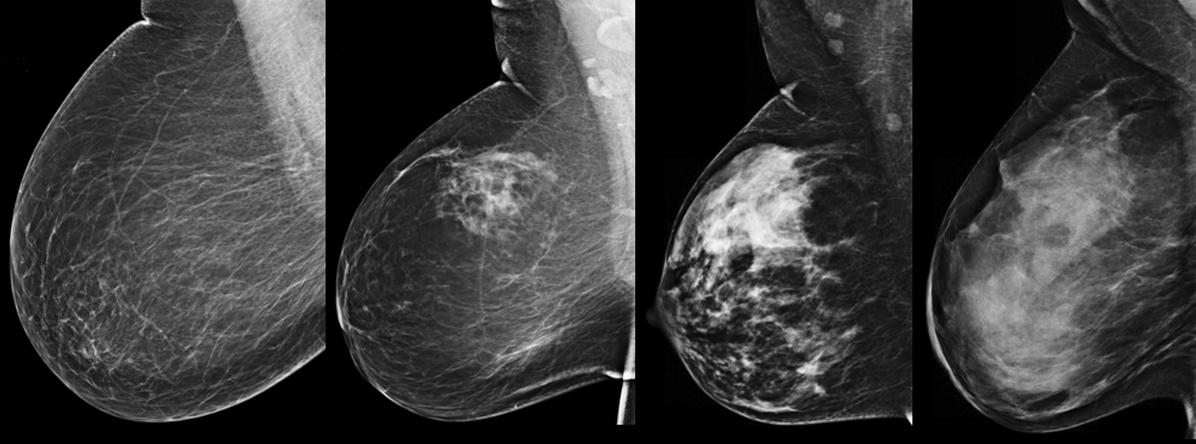

Что такое маммография: важность, процесс и результаты

Раздел: Необычные решения